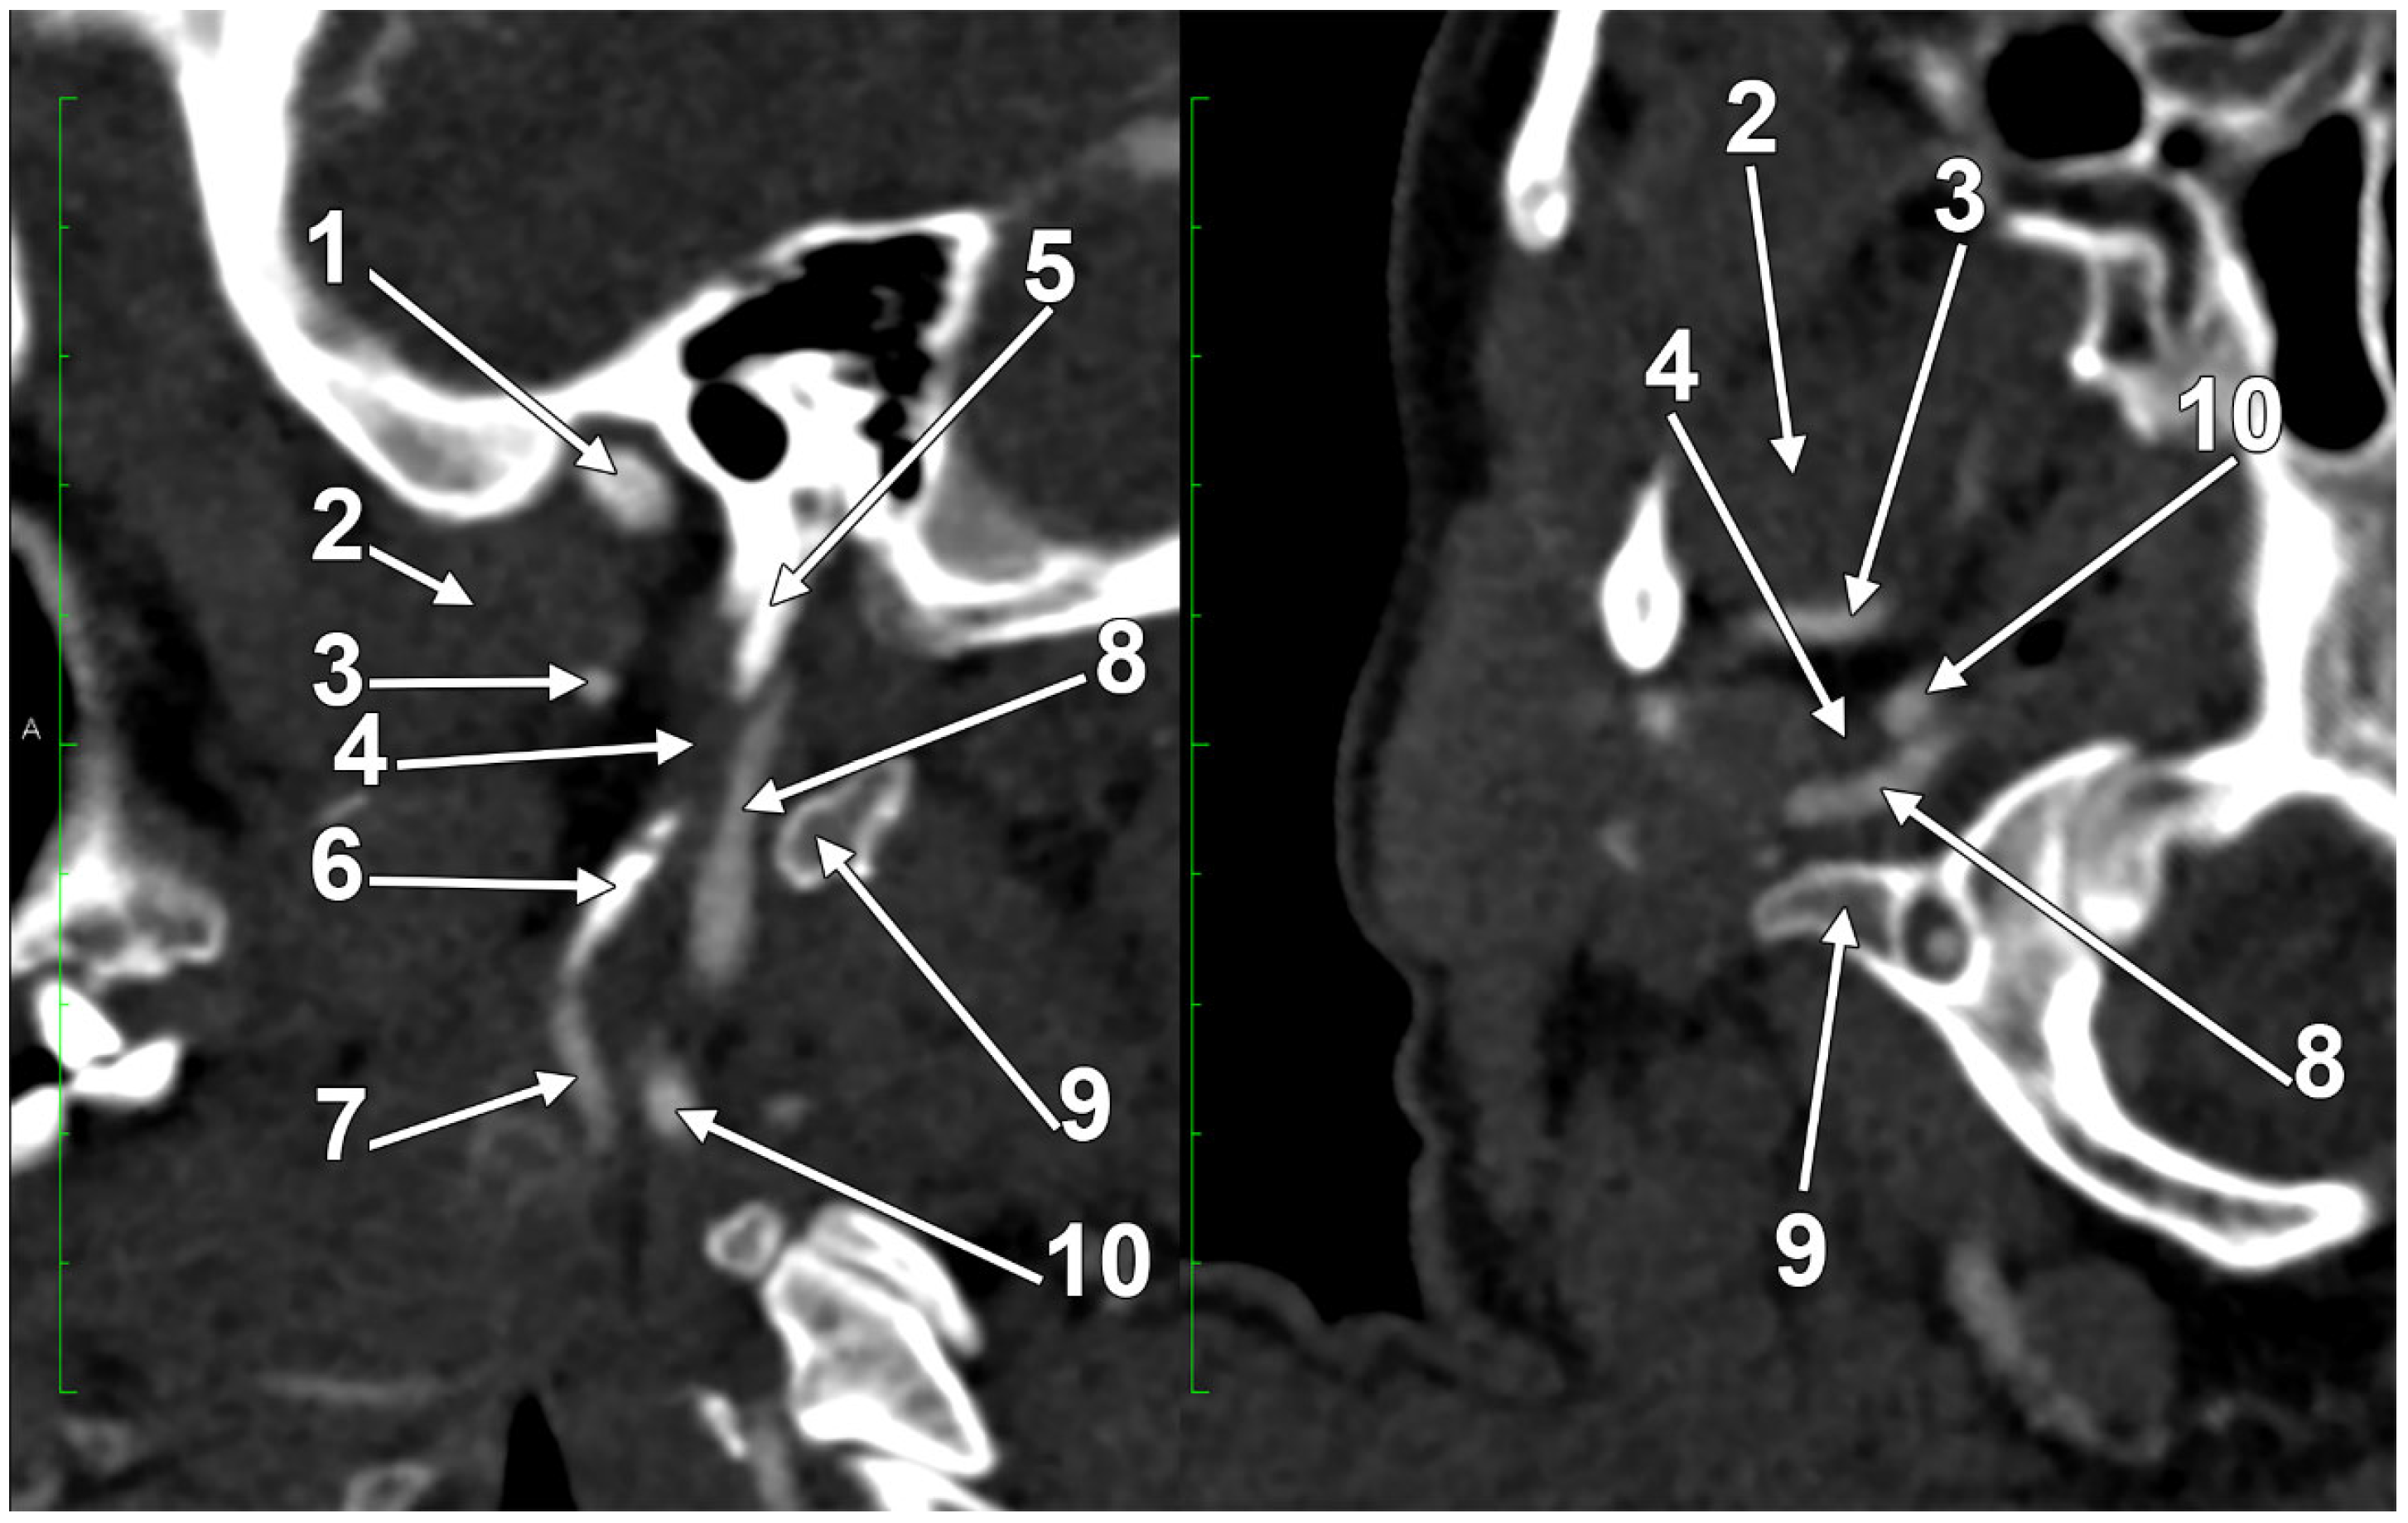

At C1, the IJV descends through a veritable vertical tunnel bordered by different anatomical structures, each of these having the potential to compress the IJV. The tunnel of the IJV is limited: posteriorly, by the C1 transverse process, through which courses the vertebral artery, anteriorly, by the SP, medially, by the ICA, antero-medially, by the stylopharyngeus and styloglossus, laterally, by the posterior belly of the digastric muscle, the SCM, and, eventually, the mastoid process, and anterolaterally, by the deep lobe of the parotid gland and the external carotid artery (ECA) (Figure 1). A retrostyloid course of the ECA [46] will bring it between the SP and the IJV (Figure 2).

We present here a case with bilateral long IPSs (Figure 7 and Figure 8). The novelty lies in the fact that both the long IPS and the IJV were pinched within the C1/SP nutcracker. This is because, on the one hand, the stenosis of the IJV determines different neurological deficits, discussed elsewhere in this paper, and, on the other hand, a compressed IPS could not be of use as an endovascular passage when it is compressed into a nutcracker. Specific documentation of IPS compression between the SP and atlas appears to be either very rare in the literature or potentially underreported. During an anatomical study of the archived angioCT file of a 63-year-old male case, bilateral long IPSs were found. The right one was 1.25 cm long, and the left one was 5.15 cm long. The right one had a diameter of 0.2 cm. The opposite one had a diameter of 0.32 cm. The right IPS was joined beneath the jugular foramen by the lateral condylar vein. The left IPS descended antero-medially to the left IJV. Both these veins were applied and compressed on the anterior side of the transverse process of the atlas. The two veins continued anterolaterally to the transverse process of the axis, and at 0.41 cm below that process, the IPS ended into the IJV. On both sides, the ICAs crossed anteriorly to the IPSs to enter the carotid canals. Therefore, the anatomic route of the IPS, the long IPS-to-IJV confluence site, and the diameter of the IPS are relevant in clinical procedures, such as cavernous sinus sampling, which requires catheterisation of both IPSs. Knowledge of the venous anatomy, including variants of the IPS and its branches, is crucial for the diagnosis and treatment of parasellar lesions.